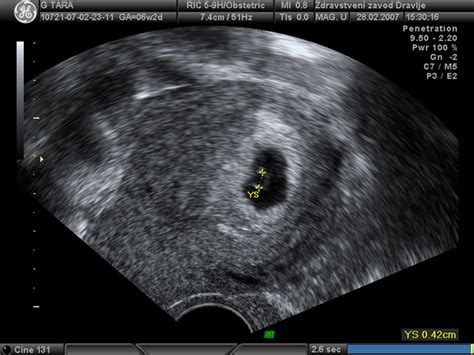

Pomembna novost v tem obdobju je razvoj brbončic. Nekateri celo menijo, da sedaj malček v plodovnici že lahko okusi, kaj jeste! Poleg tega se noge rastejo in postajajo daljše od rok, plod lahko premika vse sklepe in okončine. Na ultrazvočnem pregledu lahko vidimo, da sesa palec. Lahko začuti močno svetlobo od zunaj, stisne pest, se refleksno smeji. V tem času se razvijajo tudi mišice obraza, kar omogoča že nekatere osnovne obrazne izraze.

Verjetno se tega niti ne zavedate, a v vas raste pravcati mali čudež. Nuhalna svetlina in hormonski testi so že za vami, pred vami je tako sam še en ključni pregled, ki vas čaka okrog 20. tedna, “morfologija”, kjer podrobneje pregledajo različne dele telesa. Med 15. in 20. tednom se opravi tudi amniocenteza, s pomočjo katere je mogoče ugotoviti več sto genetskih in kromosomskih motenj.